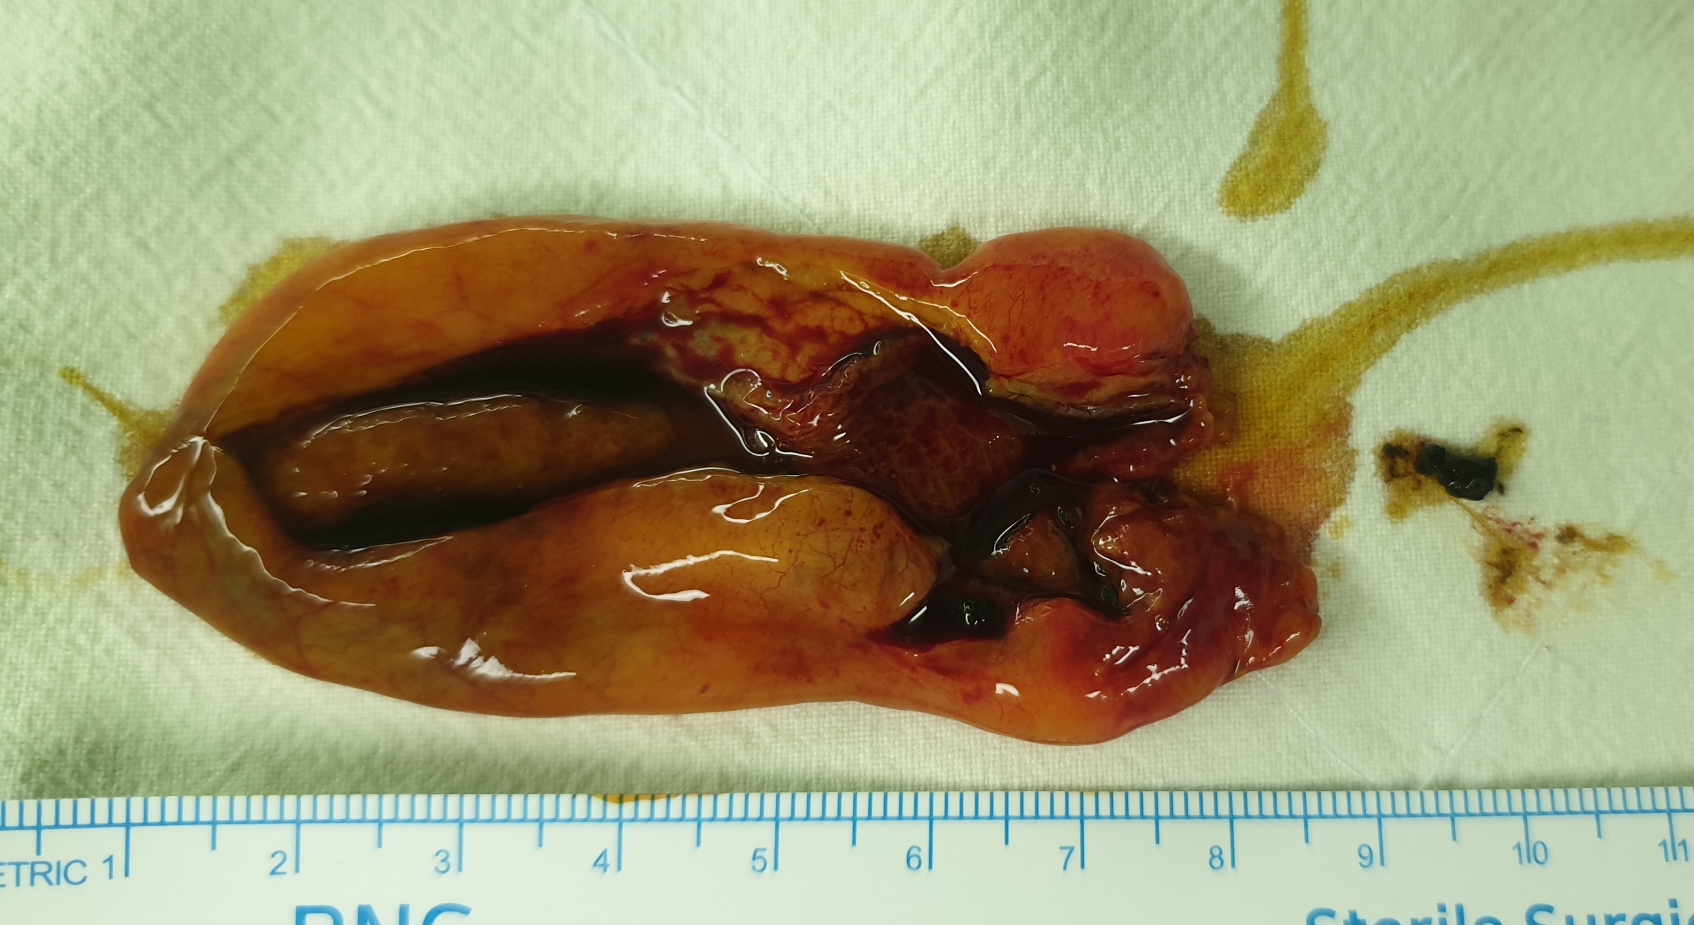

환자분은 경주에 사시는 분인데 2월말 경에 복통이 심해서 동국대학병원에 가셔서 복부 CT를 시행후에 급성 담낭염으로 담낭절제 수술을 권유받으셨다고 합니다.

그 당시에 황달 수치도 높았고 췌장염도 동반되어 있었습니다.

방금 복강경 담낭절제술을 시행했고 수술은 20분 걸렸습니다.